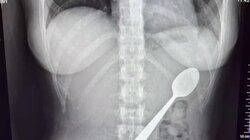

Σπέρμα από Δανό δότη που έφερε γενετική μετάλλαξη η οποία αυξάνει τον κίνδυνο εμφάνισης καρκίνου χρησιμοποιήθηκε για τη σύλληψη σχεδόν 200 παιδιών παγκοσμίως, αποκάλυψε σήμερα έρευνα του δημόσιου ραδιοτηλεοπτικού φορέα DR της χώρας.

"Τουλάχιστον 197 παιδιά γεννήθηκαν χρησιμοποιώντας σπέρμα από έναν ανώνυμο Δανό δότη γνωστό ως Κγελντ, προτού η τράπεζα σπέρματος ανακαλύψει μια σοβαρή γενετική ανωμαλία", ανέφερε ο DR, ο οποίος διεξήγαγε την έρευνα σε συνεργασία με 13 άλλους ευρωπαϊκούς δημόσιους ραδιοτηλεοπτικούς φορείς.